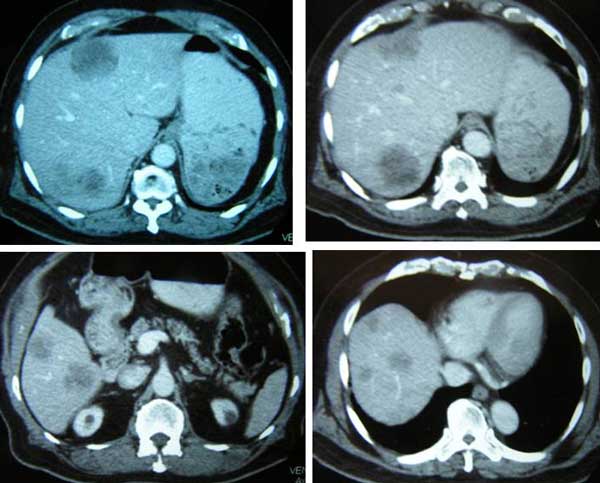

I had a chance to talk to his doctor who told me my brother had anaplastic thyroid cancer. In addition, there were extensive metastases in his lungs and liver. Without doubt – by just looking at the CT scan images (below) – I knew that his days were numbered. No treatment would be able to save him.

On top of this aggressive, rare cancer he also had metastases in his lung and liver. His metastasis was very serious indeed. There is no way anyone can pretend to be a “hero” trying to save him. Added to that was the metastasis to the liver. I was not able to know how extensive it was because I was not able to see the CT scan of his liver.